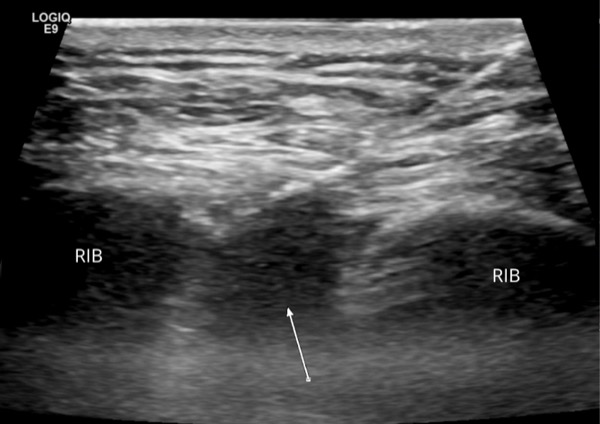

In patients undergoing abdominal wall surgery, cryoablation administered subcutaneously up to a month before surgery is showing potential to keep them numb and free of pain for weeks and possibly months after surgery, reducing or eliminating the need for narcotic painkillers while they recover, according to one institution’s experience.